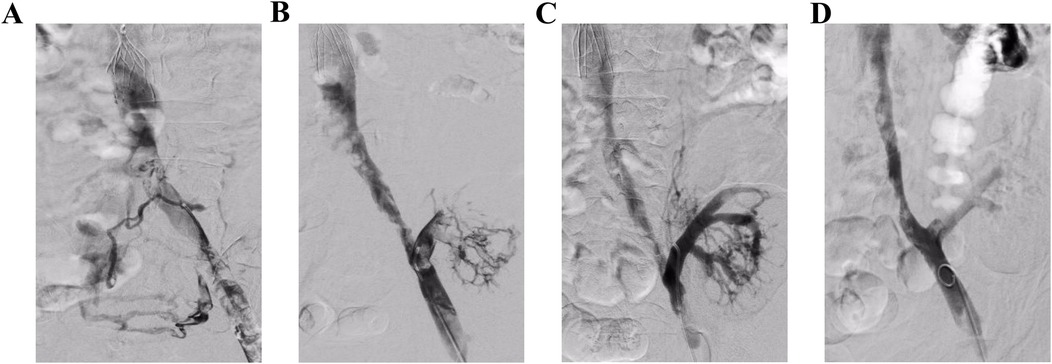

Figure 1. Angiography in operation. (A) Angiography revealed a fresh thrombosis in the left iliac vein. (B) The main and branch thrombi of the transplanted kidney vein can be seen after AngioJet thrombectomy of the left iliac vein. (C and D) The main and branches of the transplanted renal vein were well developed after AngioJet thrombectomy and the iliac vein was clear.

A 41-year-old man with a history of allogeneic kidney transplantation performed 15 years prior was admitted to our hospital due to an acute onset of left lower abdominal pain and discomfort, accompanied by significant swelling of the left lower limb lasting for 2 days. During this period, his urine output decreased sharply from approximately 1,500–2,000 to 200 mL/day. Color Doppler ultrasound indicated thrombosis from the left common femoral vein to the left common iliac vein. In addition, it indicated thrombosis formation in the left transplanted kidney vein. The results of the laboratory examination are as follows: D-dimer: 60.95 μg/mL (reference value 0–0.55 μg/mL); creatinine rose sharply from 240 μmol/L before onset to 649 μmol/L (reference value 51–97 μmol/L). Suspecting acute kidney injury of the transplanted kidney, the patient underwent surgical treatment 4 h after admission. First, an inferior vena cava (IVC) filter was inserted emergently to prevent the thrombus from moving and subsequent fatal pulmonary embolism. Then, an AngioJet thrombus aspiration catheter was used to perform a thrombectomy in the left iliac vein, left femoral vein, and transplanted kidney vein. A 5 F curved catheter with negative pressure was used to manually aspirate the thrombus from the branch of the transplanted renal vein. Angiography confirmed patency restoration of the left external iliac and common femoral veins, with no residual thrombus observed in the main trunk or branches of the transplanted renal vein (Figure 1). However, approximately 50% stenosis remained in the left common iliac vein post-thrombus removal. Then, after ATLAS balloon (16 mm × 60 mm) dilatation of the left common iliac vein, re-angiography showed that the blood supply of the left common iliac vein was significantly improved. The blood flow velocity and residual stenosis (30%) were acceptable without stent graft implantation. The patient underwent continuous renal replacement therapy (CRRT) for 3 days post-procedure. Medical management included immunosuppressants (tacrolimus, mycophenolate mofetil, and prednisone) and anticoagulation with low-molecular-weight heparin (LMWH) (enoxaparin 80 U/kg every 12 h). Clinical improvement was subsequently noted, with urine output progressively increasing to approximately 1,500 mL/day and renal function showing recovery, as evidenced by a decrease in serum creatinine to around 332 μmol/L. After discharge, anticoagulation therapy (rivaroxaban 20 mg q.d.) was prescribed for 3 months. At the 3-month follow-up, the patient's renal function had remained stable, with serum creatinine maintained around 300 μmol/L and urine output consistently between 1,500 and 2,000 mL/day (Figure 2). Postoperative surveillance with Doppler ultrasound at 1- and 3-month intervals confirmed patency without thrombosis or stenosis in the iliac venous system.